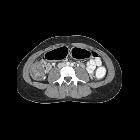

Teenager with

diarrhea and emesis. Axial CT with contrast of the abdomen shows marked thickening of the ascending colon along with multiple enlarged lymph nodes in the right lower quadrant.The diagnosis was salmonella colitis.